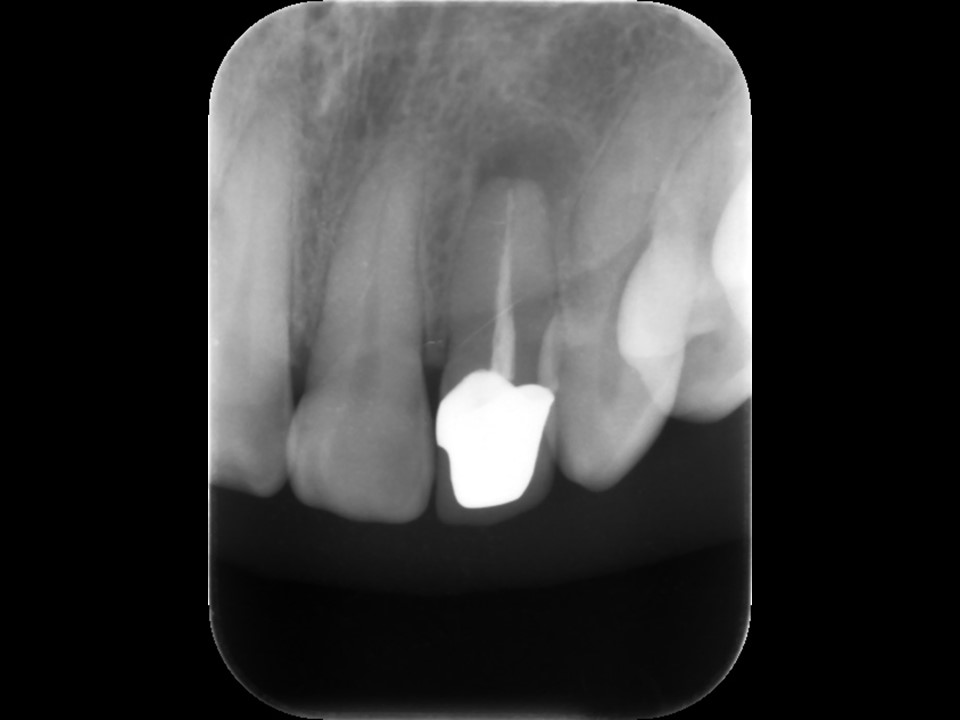

再根管治療後レントゲン。バイオセラミックとガッタパーチャによる根管充填を行った。根尖部まで緊密に薬が入っているのが分かる。このようにしっかりと根管治療を行うことで、安心して歯を被せることが出来る。